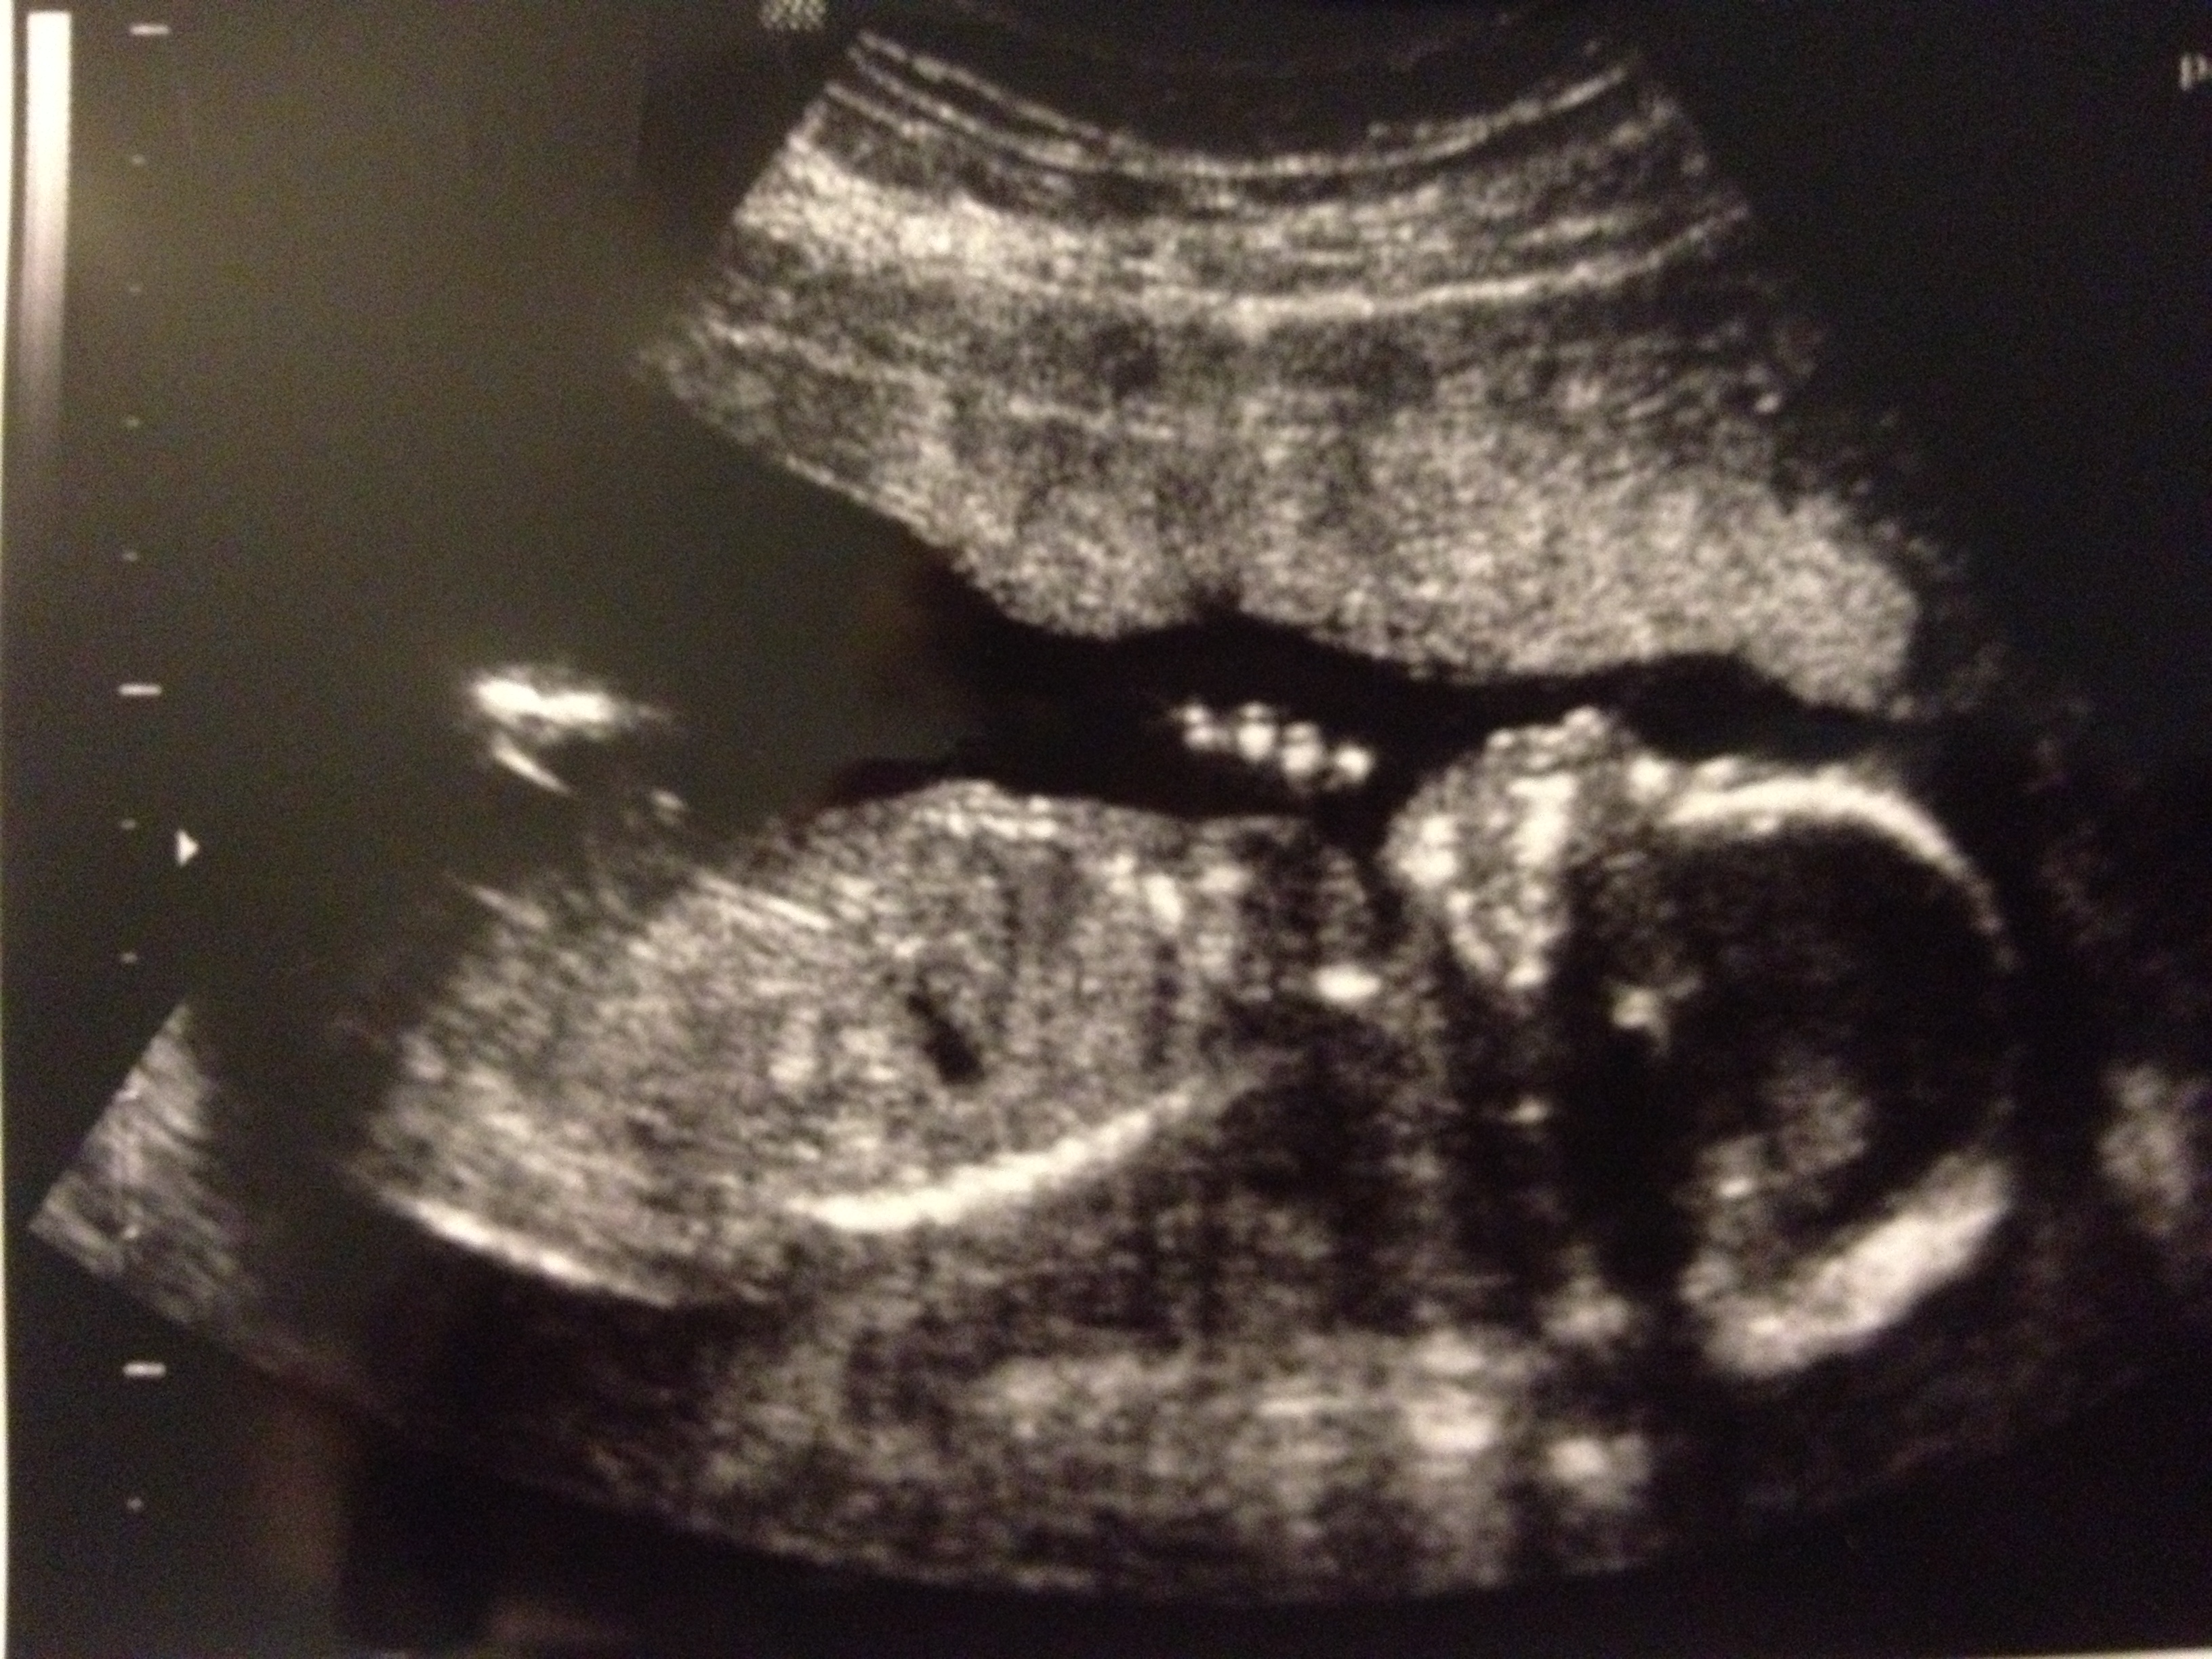

May 2014 226 May25 Published at 3264 × 2448 in St. Louis Adventure! ← Previous Next → Little profile. Placenta is anterior, which I’d already figured out, and baby was really wedged up against it interestingly.